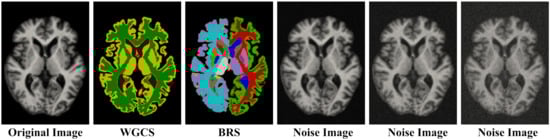

3.3. The Anti-Noise Experiments on the OASIS-1 Dataset